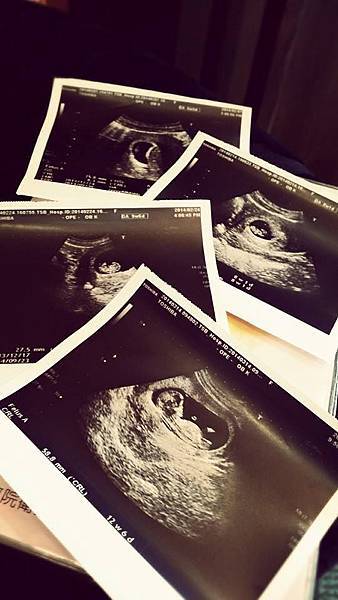

把一開始到後期的超音波照排列在一起~

真的覺得生命很奇妙!!!!

慢慢地有了小手手小腳腳~

然後強而有力的心跳聲!!!